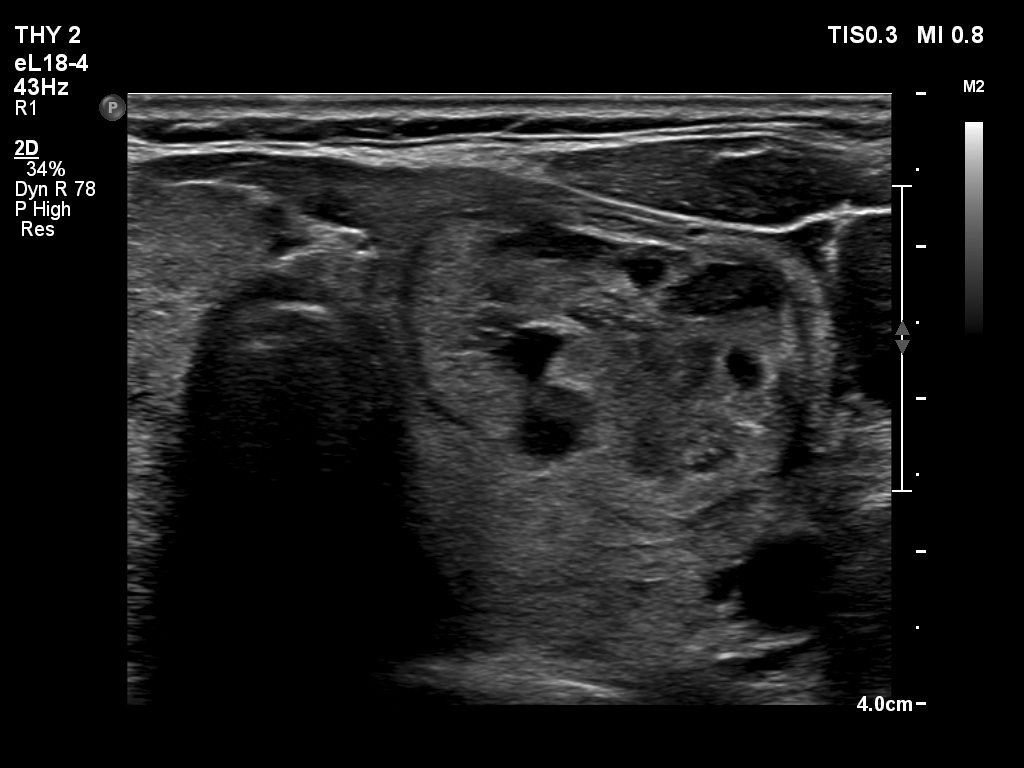

Ultrasonography. The thyroid was echonormal. The right lobe contained several discrete areas without any clinical significance. There was multi-chambered cystic nodule in the left lobe. The nodule had echonormal solid part and presented halo sign.

- The distinction between a multi-chambered cyst and a spongiform cyst is important, because in the latter the risk of malignancy is practically zero. In spongiform cysts almost the entire nodule is composed of cystic areas, and there is very small proportion of solid areas.